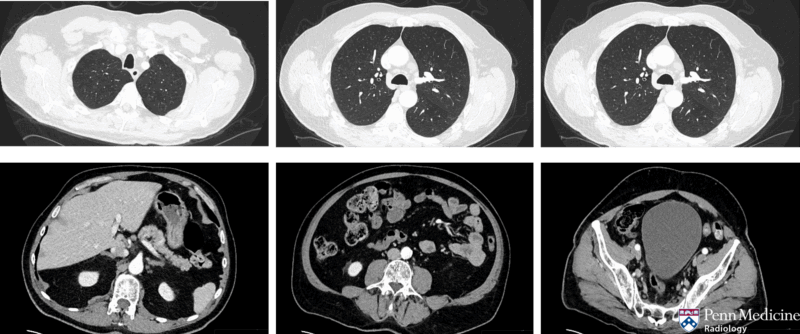

A man in his 60s, previously active in golf and pickleball, presented with difficulty standing, worsening leg weakness, paresthesias, radiating back pain, constipation, and urinary retention.